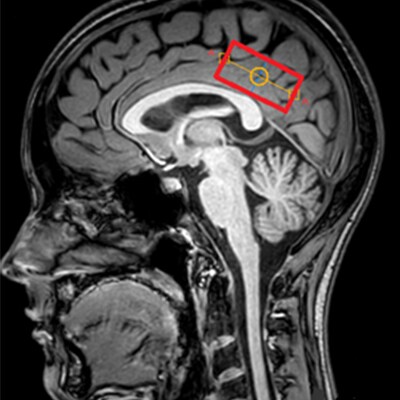

Сотрясение головного мозга у детей успешно изучают сотрудники НИИ Неотложной детской хирургии и травматологии в сотрудничестве с командой Philips Clinical Science. Ранее полученные результаты (Исследования последствий черепно-мозговых травм у детей | Philips ; Метаболические изменения белого вещества мозга | Philips ; Микроструктурные нарушения в таламусе в остром периоде сотрясения головного мозга | Philips) дополнились в 2022 году новым открытием [1]. Последовательность MEGA-PRESS и методы постобработки спектров позволили обнаружить увеличение концентрации ГАМК при неизменной концентрации глутама в задней поясной коре мозга у детей с сотрясением (рис.1).